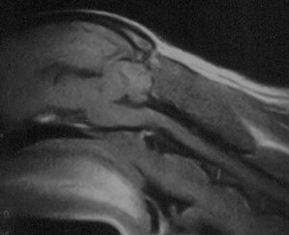

3 years old

No symptoms of SM

Mild malformation, slight

squashing/pinching of cerebellum

Probable mild dilatation of the central

canal

Medulla kinked/squashed

You can also see the vertebrae. They are the white lines that look almost like pointers

underneath the spinal cord. Three are visible.

One (C1) is below the cerebellum where

the spinal cord begins

The other two are further back--C2 and C3